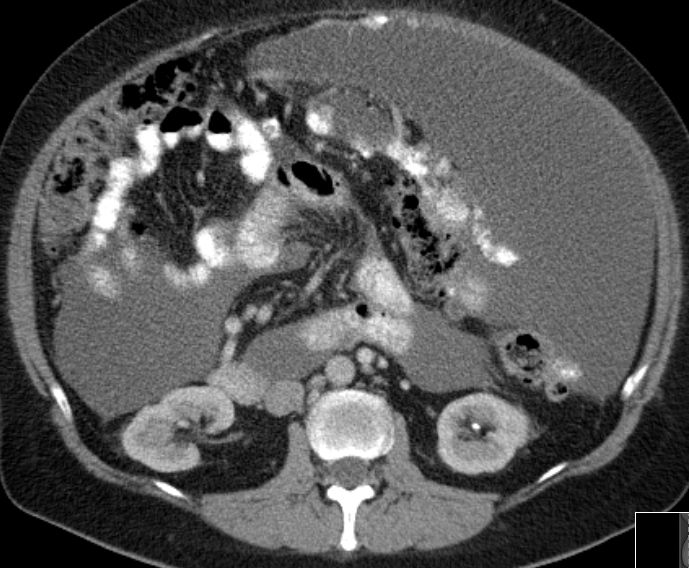

| Fall 1 | 51-jährige Frau mit primärem Peritonealkarzinom. | |||

| Therapie: Partielle Peritonektomie, HE mit Adnexen, Sigmaresektion (Hartmann), Omentumresektion. | Histologisch: Gut differenziertes seröses Adenokarzinom mit massenhaft Psammomkörperchen (Psammokarzinom). G1.Staging: pT3c. | |||